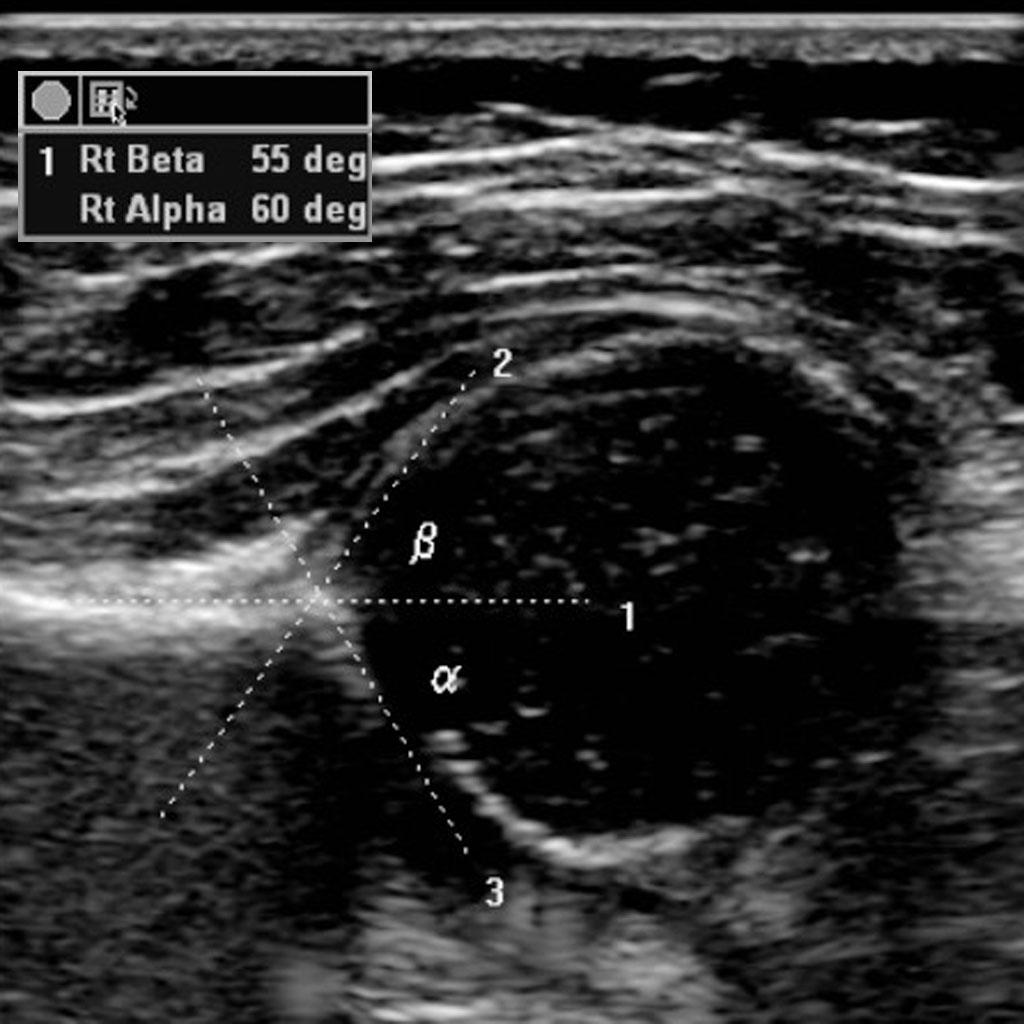

Neonatal Hip normal – ULTRASOUNDPAEDIA | Neonat…

normal-infant-hip-ultrasound - Don't Forg…